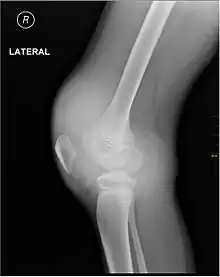

يدل النزف العضلي ونزف المفاصل (تدمي المفصل) على الهيموفيليا،[7] في حين أن نزف الجهاز الهضمي والنزيف الدماغي يكون ذات صلة باضطرابات التخثر الأخرى. وعلى الرغم من أن النزف المفصلي ليس مهددا للحياة، إلا أنه من أخطر أعراض الهيموفيليا. فقد يسبب النزيف المتكرر في محفظة المفصل تلف دائم وتشوه للمفصل، مما يؤدي إلى التهاب المفاصل المزمن والعجز. لا يحدث تلف المفصل نتيجة وجود دم في المحفظة، ولكن بسبب عملية الالتئام. عندما يتم تكسير الدم الموجود في المفصل بواسطة إنزيمات الجسم، يتم أيضا تكسير العظام في تلك المنطقة، مما يسبب الكثير من الألم للشخص المصاب بالمرض.